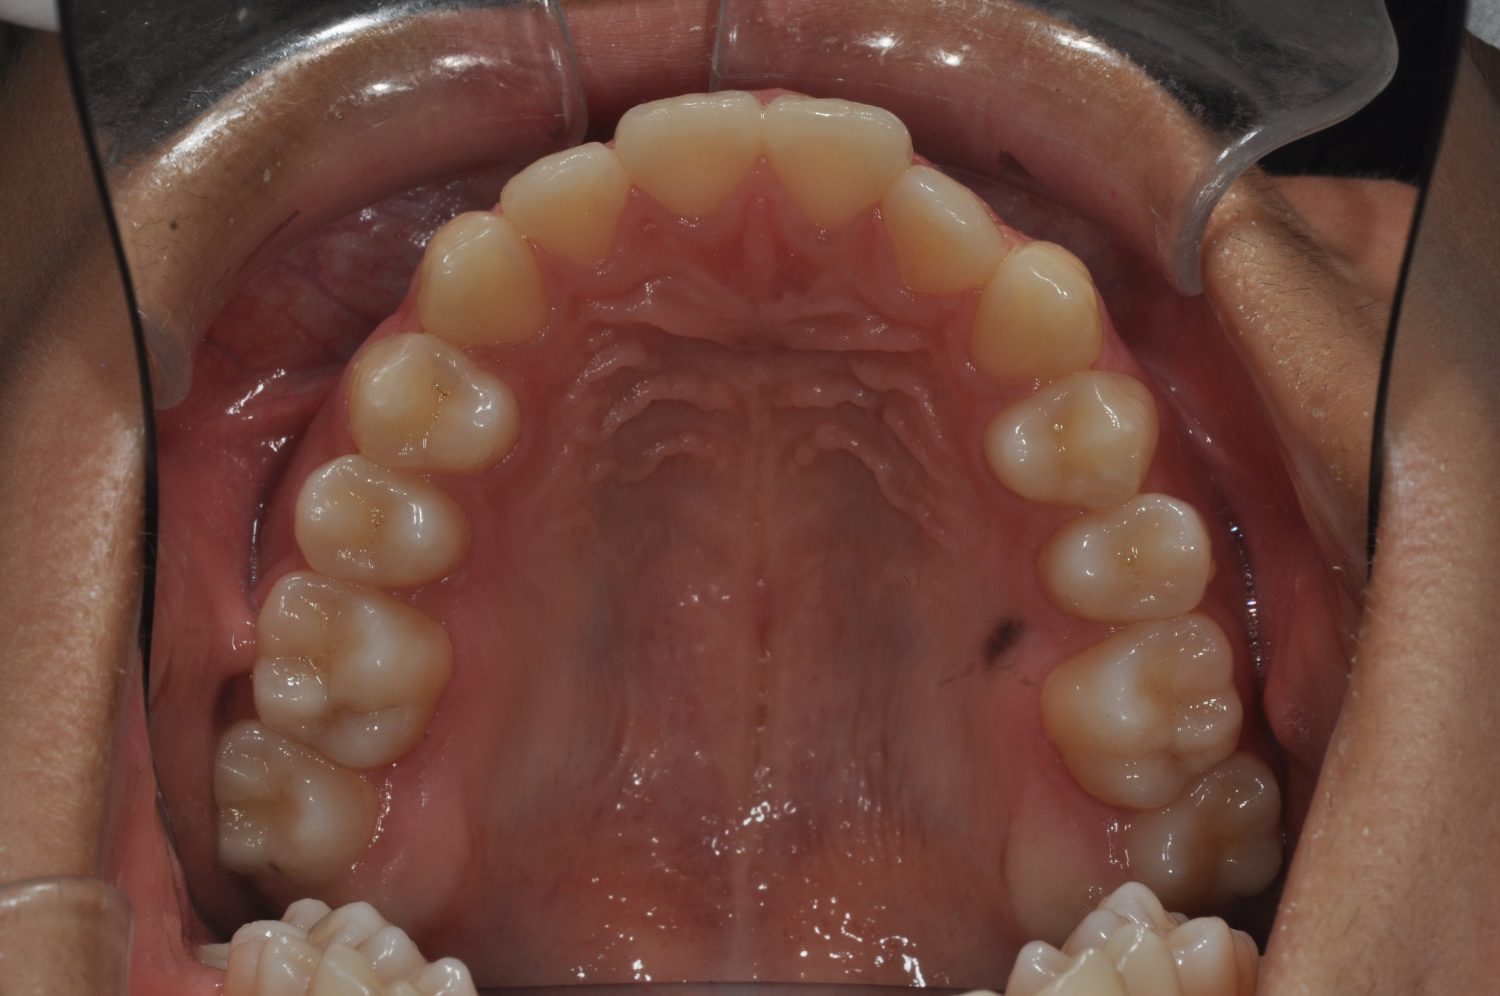

| 主訴 | 口上下顎のガチャガチャが気になる |

| 治療内容 | 歯冠幅径が大きいことから、IPRを併用した非抜歯治療 |

| 治療期間 | 1年2ヶ月 |

| 想定されたリスク | 矯正中の清掃状況によってはむし歯や歯周病のリスクがありました。歯根吸収や歯肉退縮のリスクもありました。 |

Ⅰ期治療で前歯部反対咬合をセクショナルアーチとMPAを使用して改善した後、成長観察を行っていました。永久歯が萌出したため、Ⅱ期治療を開始することとなった。上下顎とも骨格的に問題がなかったため、非抜歯で治療を行った。